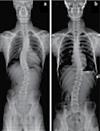

38 콜로라도 타임즈 · 2023년 5월 18일 목요일 · 1077호 교통사고 후유증 / 목 통증 / 목 디스크 / 오십견 / 어깨통증 말초신경장애: 손, 발, 다리의 통증, 저림, 근육약화감, 감각상실 (편)두통 / 불면증 / 어지러움 / 턱관절 장애(TMJ) 척추측만증(Scoliosis) / 척추협착증 / 허리수술 후유증 허리통증 / 허리 디스크 / 관절염 / 좌골신경통 / 고관절, 발목, 손목 통증 ▪ ▪ ▪ ▪ ▪ ▪ ▪ ▪ ▪ 최첨단 목/허리 디스트 치료기기 최신형 디지털 X-ray 시설 Therapeutic Massage ▪초음파, 전기치료 Gonstead Chiropractic 교정치료 치료 진료과목 교통사고 치료 전문 자동차 보험 건강 보험 상해 보험 Southern California University of Health Science Doctor of Chiropractic 콜로라도주 척추신경 보드 정회원 캘리포니아주 척추신경과 보드 정회원 National Board 척추신경과 정회원 손석기 D.C. 원장, 척추신경 전문의 chiro1health@gmail.com Open Hours 월/수/금 9am-6pm 화/목: 2pm-6pm 청소년을 위한 척추교정 프로그램